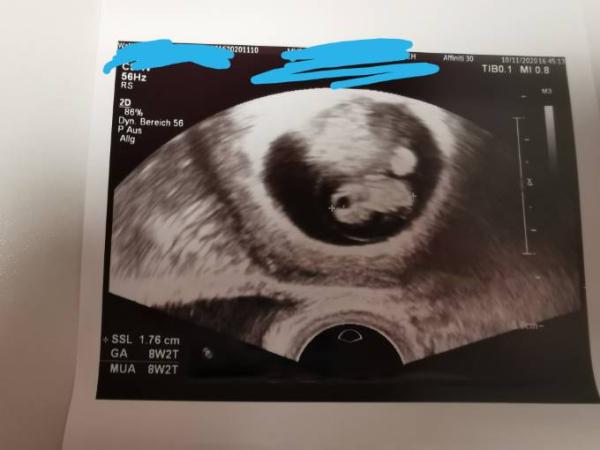

Ich hatte nun auch endlich meinen ersten Termin und wurde auch wohl noch eine Woche vor gesetzt Am Donnerstag morgen muss ich zur ersten großen Vorsorgeuntersuchung!

Bild zu Erster Termin - Forum für Juni - Mamis